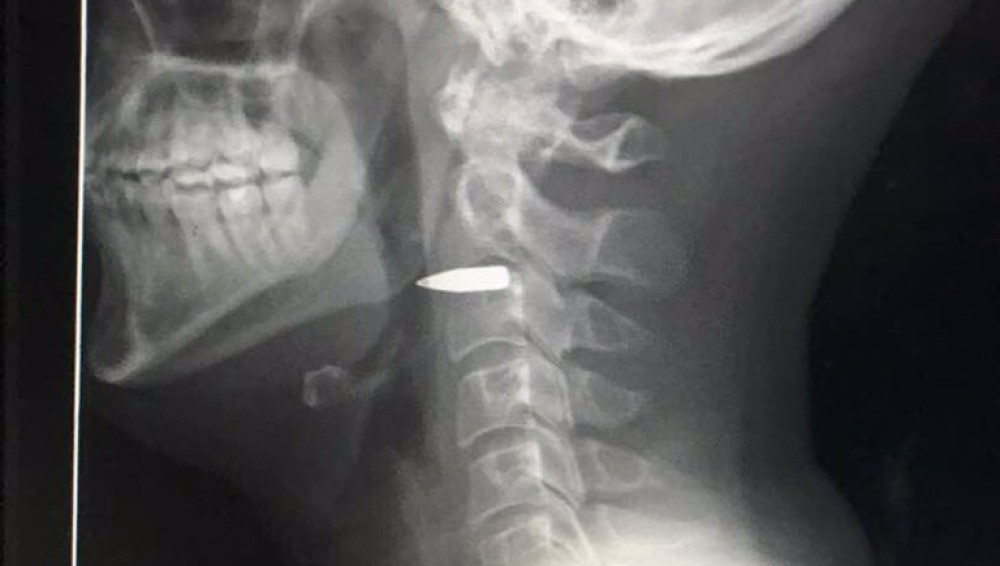

"Gracias a todos, estoy bien. La bala está aún en mi cuello, pero no impactó en nada importante", contó el periodista australiano Adam Harvey en su cuenta de Twitter.

El reportero compartió una imagen de la radiografía en la que se observa la bala alojada en su cuello.

Luego del incidente, Adam fue trasladado de urgencia a un hospital, donde le hicieron la radiografía.